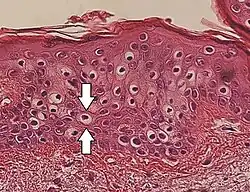

Вакуолизация (вакуольное или водяночное перерождение) — патологическое изменение клеток организма, заключающееся в появлении в их протоплазме или ядре одного или нескольких пузырьков-вакуолей, содержащих прозрачную, водяночную жидкость[1].

Вакуолизация зависит от нарушений диффузионного обмена между клеткой и окружающей её средой; чаще всего она имеет место при обильном пропитывании тканей жидкостью (при отёках, воспалении и т. п.)[2][1].